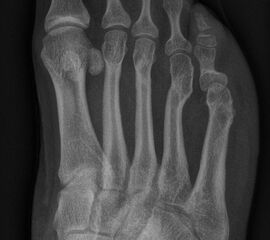

In der Regel bestehen aktive Wachstumsfugen bei Mädchen bis zum 12. und bei Jungen bis zum 14. Lebensjahr, mit Abweichungen von einem Jahr nach unten und nach oben. Präzise Informationen unter anderem darüber gibt das präoperative Röntgenbild (Abb. 2).

Abb. 2 a-c: offene Wachstumsfugen MT I Basis und Zehen (a), teilweise geöffnete Wachstumsfugen (b) und geschlossene Wachstumsfugen (c).

Zum Lesen der Bildbeschreibung und zur Vollansicht bitte die Bilder anklicken. Bilder: A. Helmers.

Die erforderlichen Osteotomien sind daher dem Fugenverlauf anzupassen, diese sind unbedingt zu respektieren. Wird eine Wachstumsfuge versehentlich mit der Fräse verletzt, kann durch partiellen oder kompletten Fugenverschluss ein Fehlwachstum provoziert werden. Achsabweichungen oder ein Wachstumstopp der betroffenen Region können die Folge sein. Offene Wachstumsfugen begrenzen die Osteotomieausrichtung besonders im Bereich des dorsalen Calcaneus, der Metatarsale I Basis und der IV. oder V. Zehe im End- und Mittelglied.